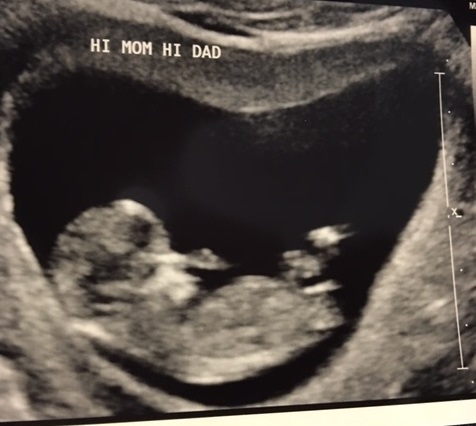

@kfras this was my babe at 11 weeks or so. Definitely starting to look more like a baby, he/she was moving around and kicking, waving etc. at that ultrasound as well.

@chicandbubbly - so crazy that you can see cute fingers and toes this early! That is a beautiful/handsome gummy bear! ...can't remember if you know if it's a boy or girl...